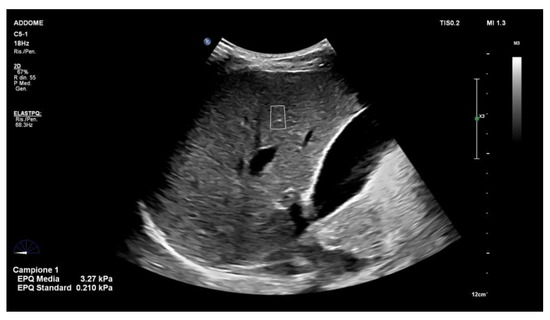

4. Liver Ultrasound Elastography in NAFLD Patients: Point Shear Wave Elastography (pSWE)